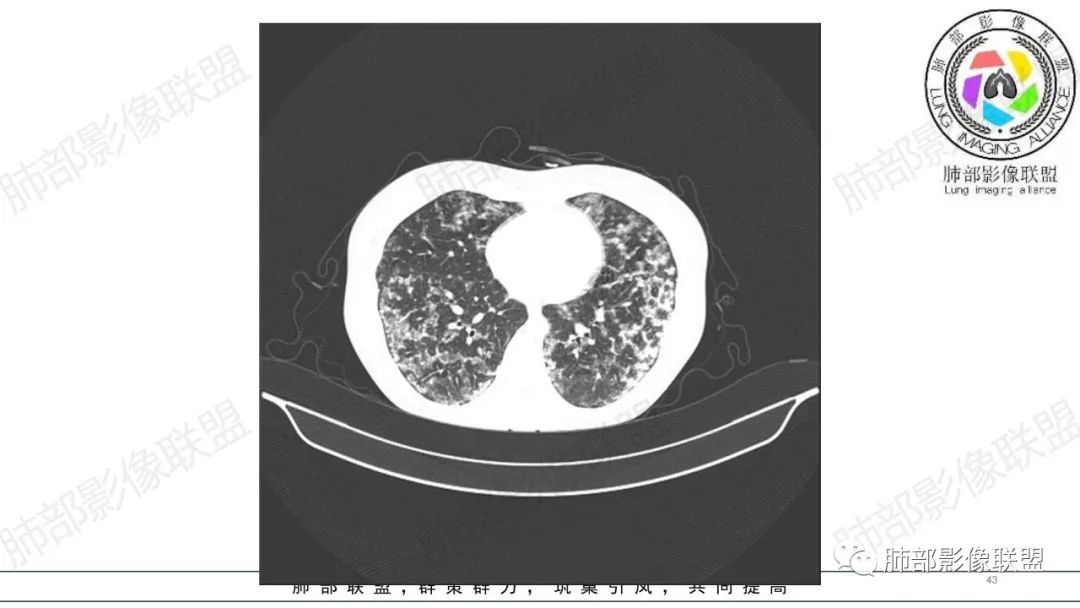

34岁女性患者,“哮喘”病史30年,近期有可疑刺激性气体吸入史;因乏力半年,咳嗽、憋气、发热4天就诊;6.1CT提示双肺广泛毛玻璃影及粟粒样结节,胸膜下闲置及血管周闲置,可见树丫征,部分小叶间隔增厚。考虑:1.过敏性肺泡炎,有可疑刺激气体接触史,胸膜下闲置,广泛毛玻璃影,地图样分布,粟粒结节边界模糊,支持过敏性肺泡炎,但糖皮激素治疗效果不佳,且动态复查血常规血红蛋白进行性降低,过敏性肺泡炎 不符合;2.肺含铁血黄素沉积症:患者30“哮喘”病史,可能为肺含铁症状,肺部CT提示双肺弥漫毛玻璃影及粟粒结节影,中下肺明显,肺底部分小叶间隔增厚,近期咳嗽、憋气、发热,血常规血红蛋白进行性下降,考虑肺含铁急性期症状,但临床无咯血症状,肺含铁不典型。综合考虑:肺含铁血黄素沉积症>过敏性肺泡炎。

年轻女性 ,急性喘息发热,肺部影像弥漫磨玻璃密度,部分细小腺泡结节,胸膜下黑线显示,短期复查,病变密度增高,下肺明显,血管周围肺组织累及较少、且逐渐成小叶间隔分布。考虑弥漫肺泡内病变,并经淋巴道转移,下肺比上肺明显,多为免疫细胞功能下肺较强。1.过敏性肺泡炎,有相关病史,三层密度特点、头尾测分布,符合。2 肺泡微石症,多有钙化,且缓慢起病,病程不太符合,放待排。3 吸入相关肺损伤,有病史,疾病演变过程也符合渗出-肉芽肿改变,建议详细询问病史。4 感染性病变,结核?病变气道分布为主,如此弥漫且没有树丫不符合。5.巨细胞病毒,可以磨玻璃 结节 改变,没有免疫缺陷病史。最后考虑吸入所致 1过敏性肺泡炎、吸入性肺损伤 鉴别肺泡微石症。

肺内气腔磨玻璃结节,肝脾肿大,治疗后间质改变,弥漫大B可能